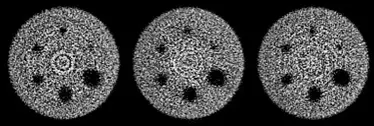

下圖SPECT切面影像之異常,最可能為下列何種原因所造成?

- 影像特徵:圖中顯示了三個 SPECT 假體(如 Jaszczak phantom,常依據假體內部不同切面顯示冷棒或冷球)的橫切面(Transverse slice)重建影像。影像中可以觀察到假體內部周邊具有射源未分佈的冷區(Cold rods/spheres)。

- 異常表現:影像中最顯著的異常是佈滿整個假體橫切面、且以旋轉中心(Center of Rotation, COR)為圓心的高頻率「同心圓狀亮暗交替條紋」。

- 臨床意義:這種異常特徵被稱為同心圓假影(Ring artifact 或 Bull's-eye artifact)。在 SPECT 造影中,這是極為經典的假影類型,會嚴重干擾病灶的判讀,甚至產生偽陽性或偽陰性結果。

- (B) 不均勻度問題:正確。當伽馬攝影機(Gamma camera)的偵檢器存在不均勻性(例如光電倍增管 PMT 老化或校正不良、閃爍晶體輕微缺陷、準直儀網格受損等),會導致特定區域的像素靈敏度異常偏高或偏低。在 SPECT 旋轉 360 度取像並進行反投影重建的過程中,這個固定的異常像素點會圍繞著旋轉中心(COR)持續被投影,進而在橫切面上描繪出一個圓軌跡。多個不均勻點就會形成如圖中所示的同心圓假影(Bull's-eye artifact)。

圖中展示了非常典型的「同心圓假影(Bull's-eye artifact)」。在 SPECT 造影中,由於影像是透過多個角度的平面影像(Planar projections)進行反投影重建而成,平面影像上哪怕只有 1% 到 2% 的微小不均勻度(Non-uniformity),在肉眼觀察平面假體影像時可能難以察覺,但都會在 SPECT 重建過程中被大幅放大,形成以旋轉中心為圓心的同心圓假影。

為了解決此問題並避免這類假影,SPECT 系統對偵檢器的**均勻度(Uniformity)**要求遠高於一般常規平面造影,通常需要每週或每月收集高達 3000 萬(30 M)至 1 億計數值的均勻度校正影像(High-count flood image)來生成修正矩陣(Correction matrix)。本題影像的異常特徵完美契合偵檢器不均勻所導致的現象,故最可能的原因為 (B) 不均勻度問題。